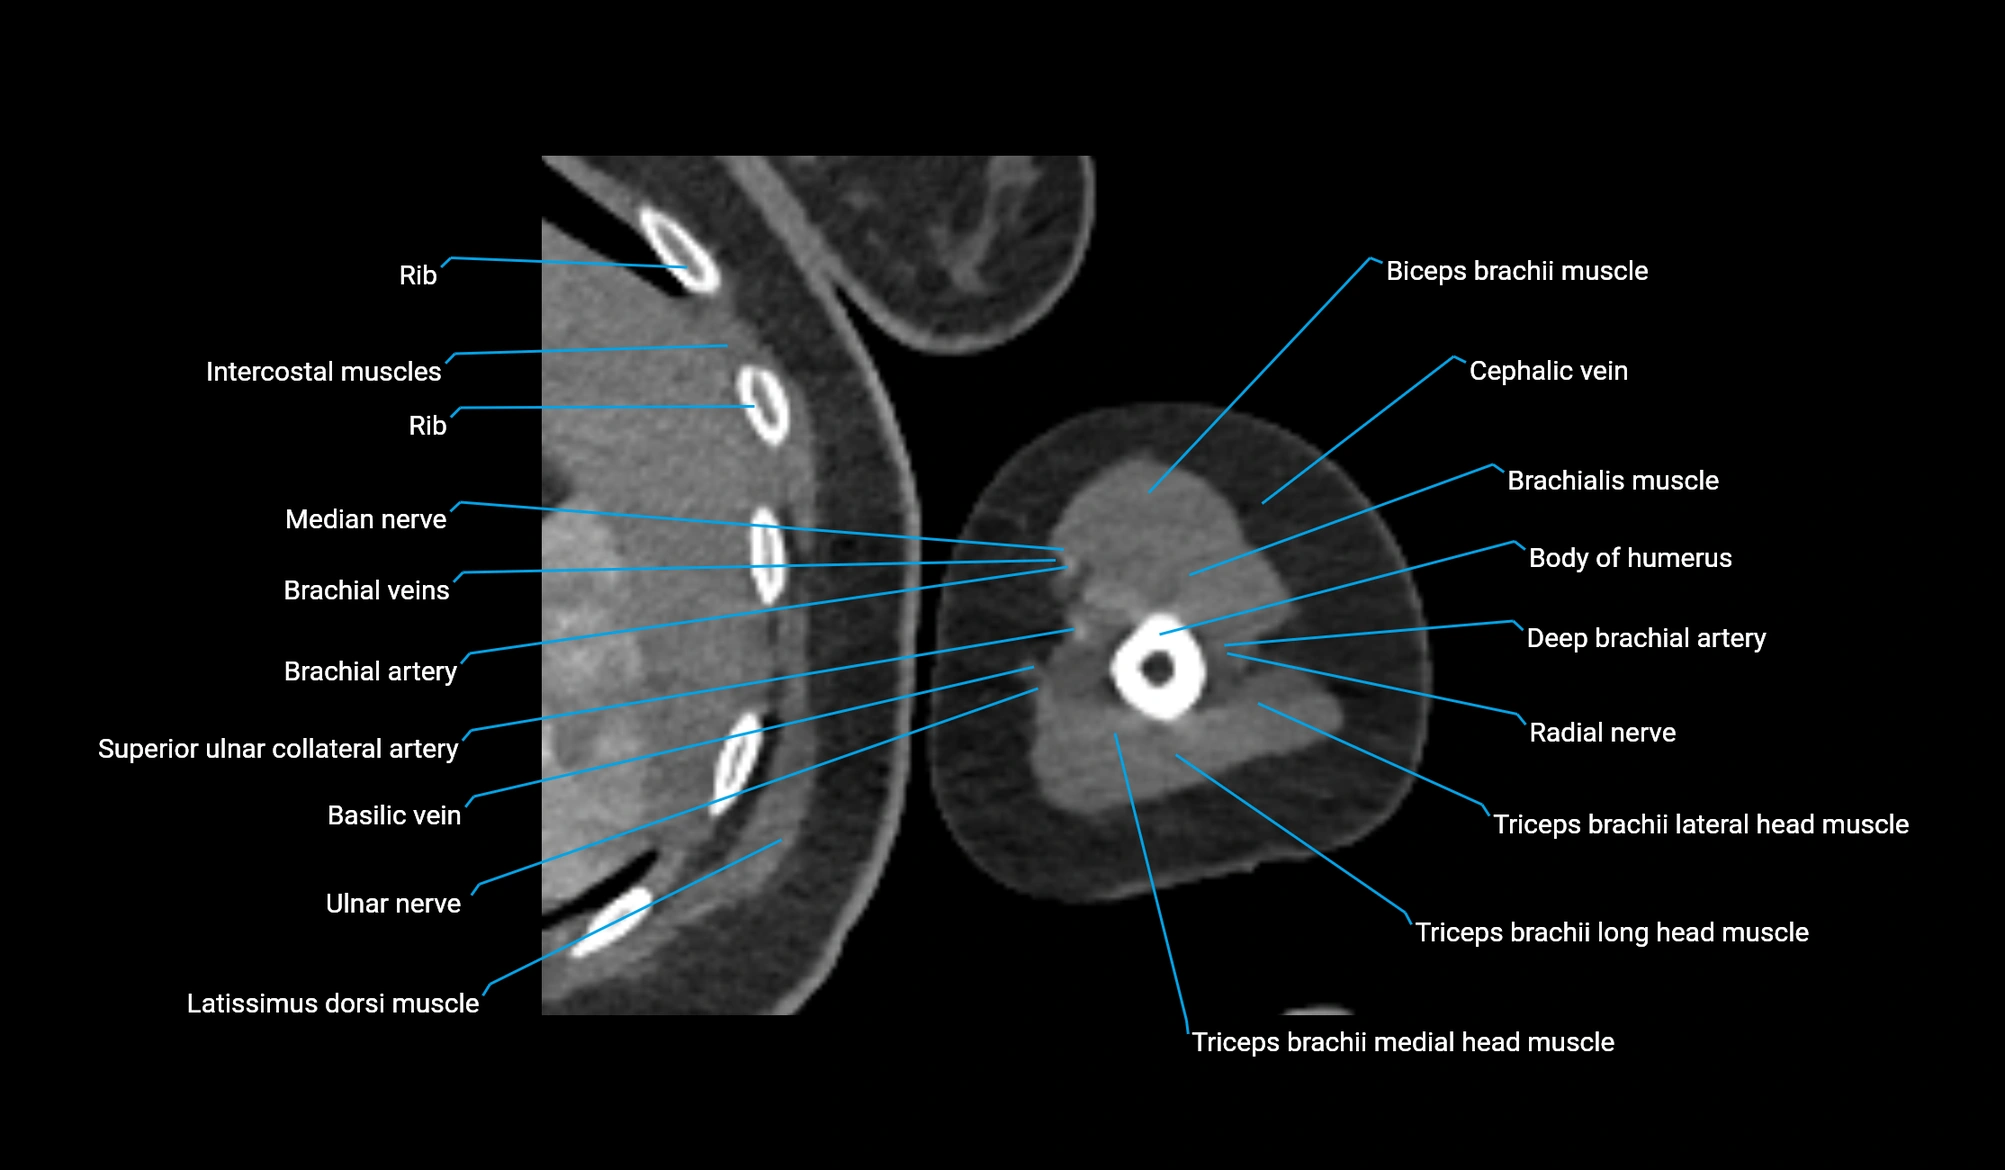

- Axillary lymph nodes

- Basilic vein

- Biceps brachii muscle

- Body of humerus

- Brachial artery

- Brachialis muscle

- Brachioradialis muscle

- Deep brachial artery

- Lateral head of triceps brachii muscle

- Long head of triceps brachii muscle

- Medial head of triceps brachii muscle

- Median nerve

- Pectoralis major muscle

- Pectoralis minor muscle

- Superior ulnar collateral artery

- Teres major muscle

- Teres minor muscle

- Thoracodorsal artery

- Ulnar nerve